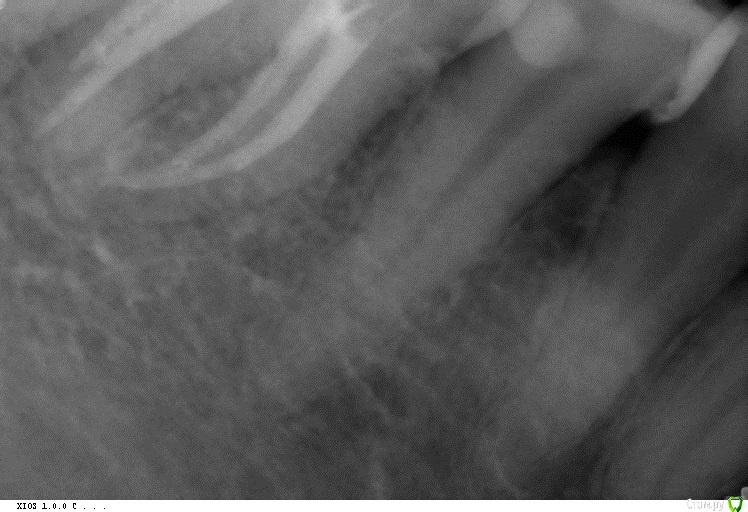

cor Опубликовано 14 июля, 2016 Поделиться Опубликовано 14 июля, 2016 Для меня F3 - слишком большое расширение устьевой и средней трети. Что бы я его засунул в канал - это исключение. Меня, как и остальных, интересует апикальная треть, а именно, как добиться адекватной ирригации в ней, родимой. Можно послушать Каплана, а можно взять эндоблок, и посмотреть (Каплан, блин, прав). Протейперы, в их классическом применении не дадут Вам возможности отмыть апикальную треть, не "убивая" анатомию канала. Но протэйперы быстро и эффективно работают в других отделах канала. А именно в устьевой и средней трети.Дальше можно подключить другие инструменты. Будь то профайлы, а может и К-3. Готовясь к "тапкам" опубликую ленивый протокол. Он работает только с опытом его использования, и пониманием, зачем)) По протоколу до протейпера F2, 30.06 профайл (35.04,40.04, 45.04 - по ситуации). Обязательно апикальный упор (калибровка гутты обязательна, только "2 конус). Ну и опыт в таких "экспериментах" заканчивался латералкой. Было здорово. Но попробуйте на удалёнках сначала, а то Мяуздрав предепреждает)) Ссылка на комментарий

St. Опубликовано 14 июля, 2016 Поделиться Опубликовано 14 июля, 2016 Протейперами работала пару лет в формате С1, С2, Ф1, дальше руками калибровать апикально.К3 и профайлами тоже работала по класической схеме.Совмещение первых и вторых по-моему логично в не сильно изогнутых каналах: первые быстро расширят устье и середину,практически не расширяя апикально, а вторые исключительно апикально и будут работать. Нагрузка на инструмент будет меньше, расширение достаточное, и по времени быстрее чем просто неагрессивными. Ссылка на комментарий

St. Опубликовано 14 июля, 2016 Поделиться Опубликовано 14 июля, 2016 Завтра гляну, спасибо) Щас уже как-то туго соображается, спать пора. Я не про то. Я про то, что апикальную треть они обрабатывают плохо, либо нам надо взять такого размера инструмент, что грозит стрип-перфо(тут уже я перегибаю Если Вы про протейперы, то так и есть. И даже не перегибаете)) пять же, мы не можем расширить устьевую и среднюю часть, и болт положить на апикальную. Но когда надо обработать апик треть - протейперы нам не помошники. Так и я о том же, что после протейперов надо допиливать, а там уже чем хотите, хоть профайлами, хоть к3, хоть ручками, хоть любыми другими файлами до приемлемого размера. Ссылка на комментарий